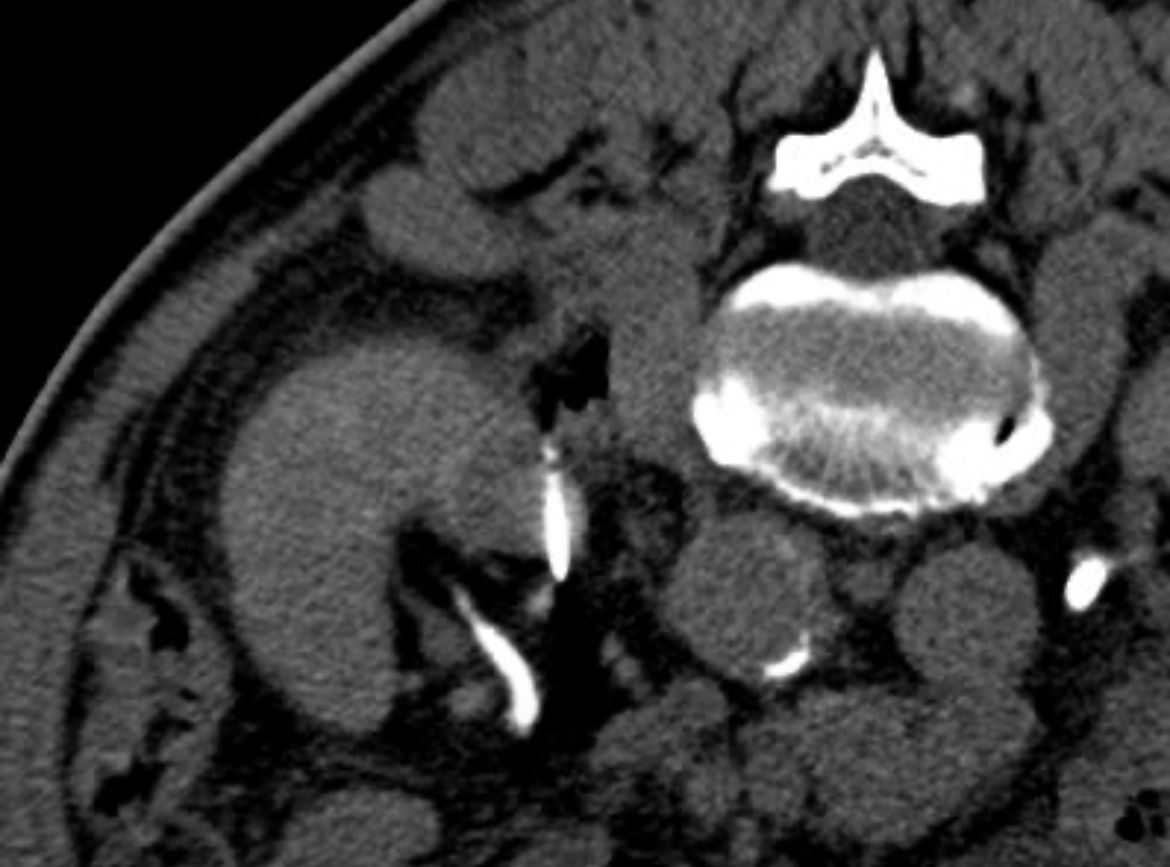

Mi actividad se centra en el tratamiento de tumores malignos óseos y viscerales (hígado, pulmón, riñón, glándulas suprarrenales, entre otros) mediante ablaciones percutáneas con microondas, crioablación, radiofrecuencia o electroporación irreversible (IRE), combinadas cuando es necesario con cementoplastia o fijación percutánea para el control local y la estabilización estructural.

Dispongo de una especial dedicación al tratamiento de las lesiones vertebrales, tanto oncológicas como osteoporóticas, empleando técnicas avanzadas de vertebroplastia, cifoplastia y sistemas de expansión e implantes vertebrales (SpineJack®, tornillos percutáneos) que permiten restaurar la estabilidad de la columna y aliviar el dolor de forma inmediata.